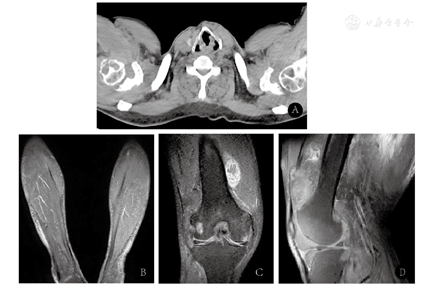

患者入院后,予完善常规检查。血尿便常规、血生化、肝肾功、凝血功能、肿瘤标记物、梅毒二项、乙肝五项、风湿系列等均未见有意义的异常指标。Pro-BNP 462 pg/ml,心脏彩超示左房扩大,室间隔增厚,二尖瓣反流(轻度),主动脉瓣硬化并返流(轻度),三尖瓣返流(轻度)。肌电图检查,示上下肢多发周围神经损伤,运动感觉均受累,部分符合长度依赖性,部分神经易卡压部位受累显著。复查电子喉镜示咽反射减弱,右侧声带活动减弱。复查右膝关节及双小腿磁共振成像(magnetic resonance imaging,MRI)检查(图2B,图2C,图2D),结果示右膝关节组成之股骨远端、胫骨近端与腓骨小头以及髌骨增生,股骨远端、胫骨近端多发片状质子密度加权像(proton density weighted image,PDWI)高信号,滑膜不规则增厚,部分呈团块状,T2WI高低混杂信号,双侧小腿软组织呈网格样改变,提示右膝病变,考虑:(1)色素沉着绒毛性结节滑膜炎;(2)滑膜软骨瘤待排。颈部、胸部CT(图2A)示颈椎周围软组织增厚,双侧胸锁关节、肩关节、胸壁软组织对称性增厚并肩关节骨质改变,纵膈及双肺门淋巴结肿大,双肺散在结节,肉芽?

结合患者的膝关节MRI及颈胸部CT肌电图检查结果,提示该患者所患为一累及多关节、周围神经、肌肉、皮肤组织的多系统受累疾病。患者舌体肥大,提示系统性淀粉样变相关肌病可能。为进一步明确诊断,予行神经、肌肉活检(图3)。肌肉活检病理(图3A)提示轻度肌源性损害,刚果红染色见淀粉样物质沉积。神经活检(图3B)刚果红染色提示小血管壁见淀粉样物质沉积。为进一步明确患者为何种类型的淀粉样物质沉积,关节病变是否为淀粉样物质沉积所导致,是否合并骨髓瘤,我们对其关节活检标本进行刚果红染色,检测其血尿轻链、血免疫固定电泳、骨髓细胞学,并对其肌肉组织进行免疫组织化学染色。关节活检标本刚果红染色(图3C)结果显示:关节腔内大量均质红染物质沉积,其在荧光显微镜下呈红色,在偏振光下呈苹果绿/苹果黄色,证实其关节病变为淀粉样物质沉积所致。血轻链示游离κ链4 755.00(3.30~19.40)mg/L,游离λ链14.80(5.71~26.30)mg/L,游离轻链κ/λ:321.2838(0.26~1.65)。尿轻链示游离κ链4 125.00 (0.39~15.10)mg/L,游离λ链5.85(0.81~10.10)mg/L,游离轻链κ/λ:705.1282(0.461~4.000)。血清免疫固定电泳示在β区可见一条单克隆轻链κ成分。对肌肉进行免疫球蛋白κ、λ链免疫组织化学染色,结果显示血管周κ链阳性沉积。骨髓细胞学示:多发性骨髓瘤,原、幼浆细胞占30%。流式细胞学示:总浆细胞占总细胞26.06%,其中95.44%表达CD38,CD138,CD56,CD117,CD27dim,不表达CD19,CD45,CD81,符合异常浆细胞表型。骨髓活检示:符合异常浆细胞增生,不除外骨髓瘤。